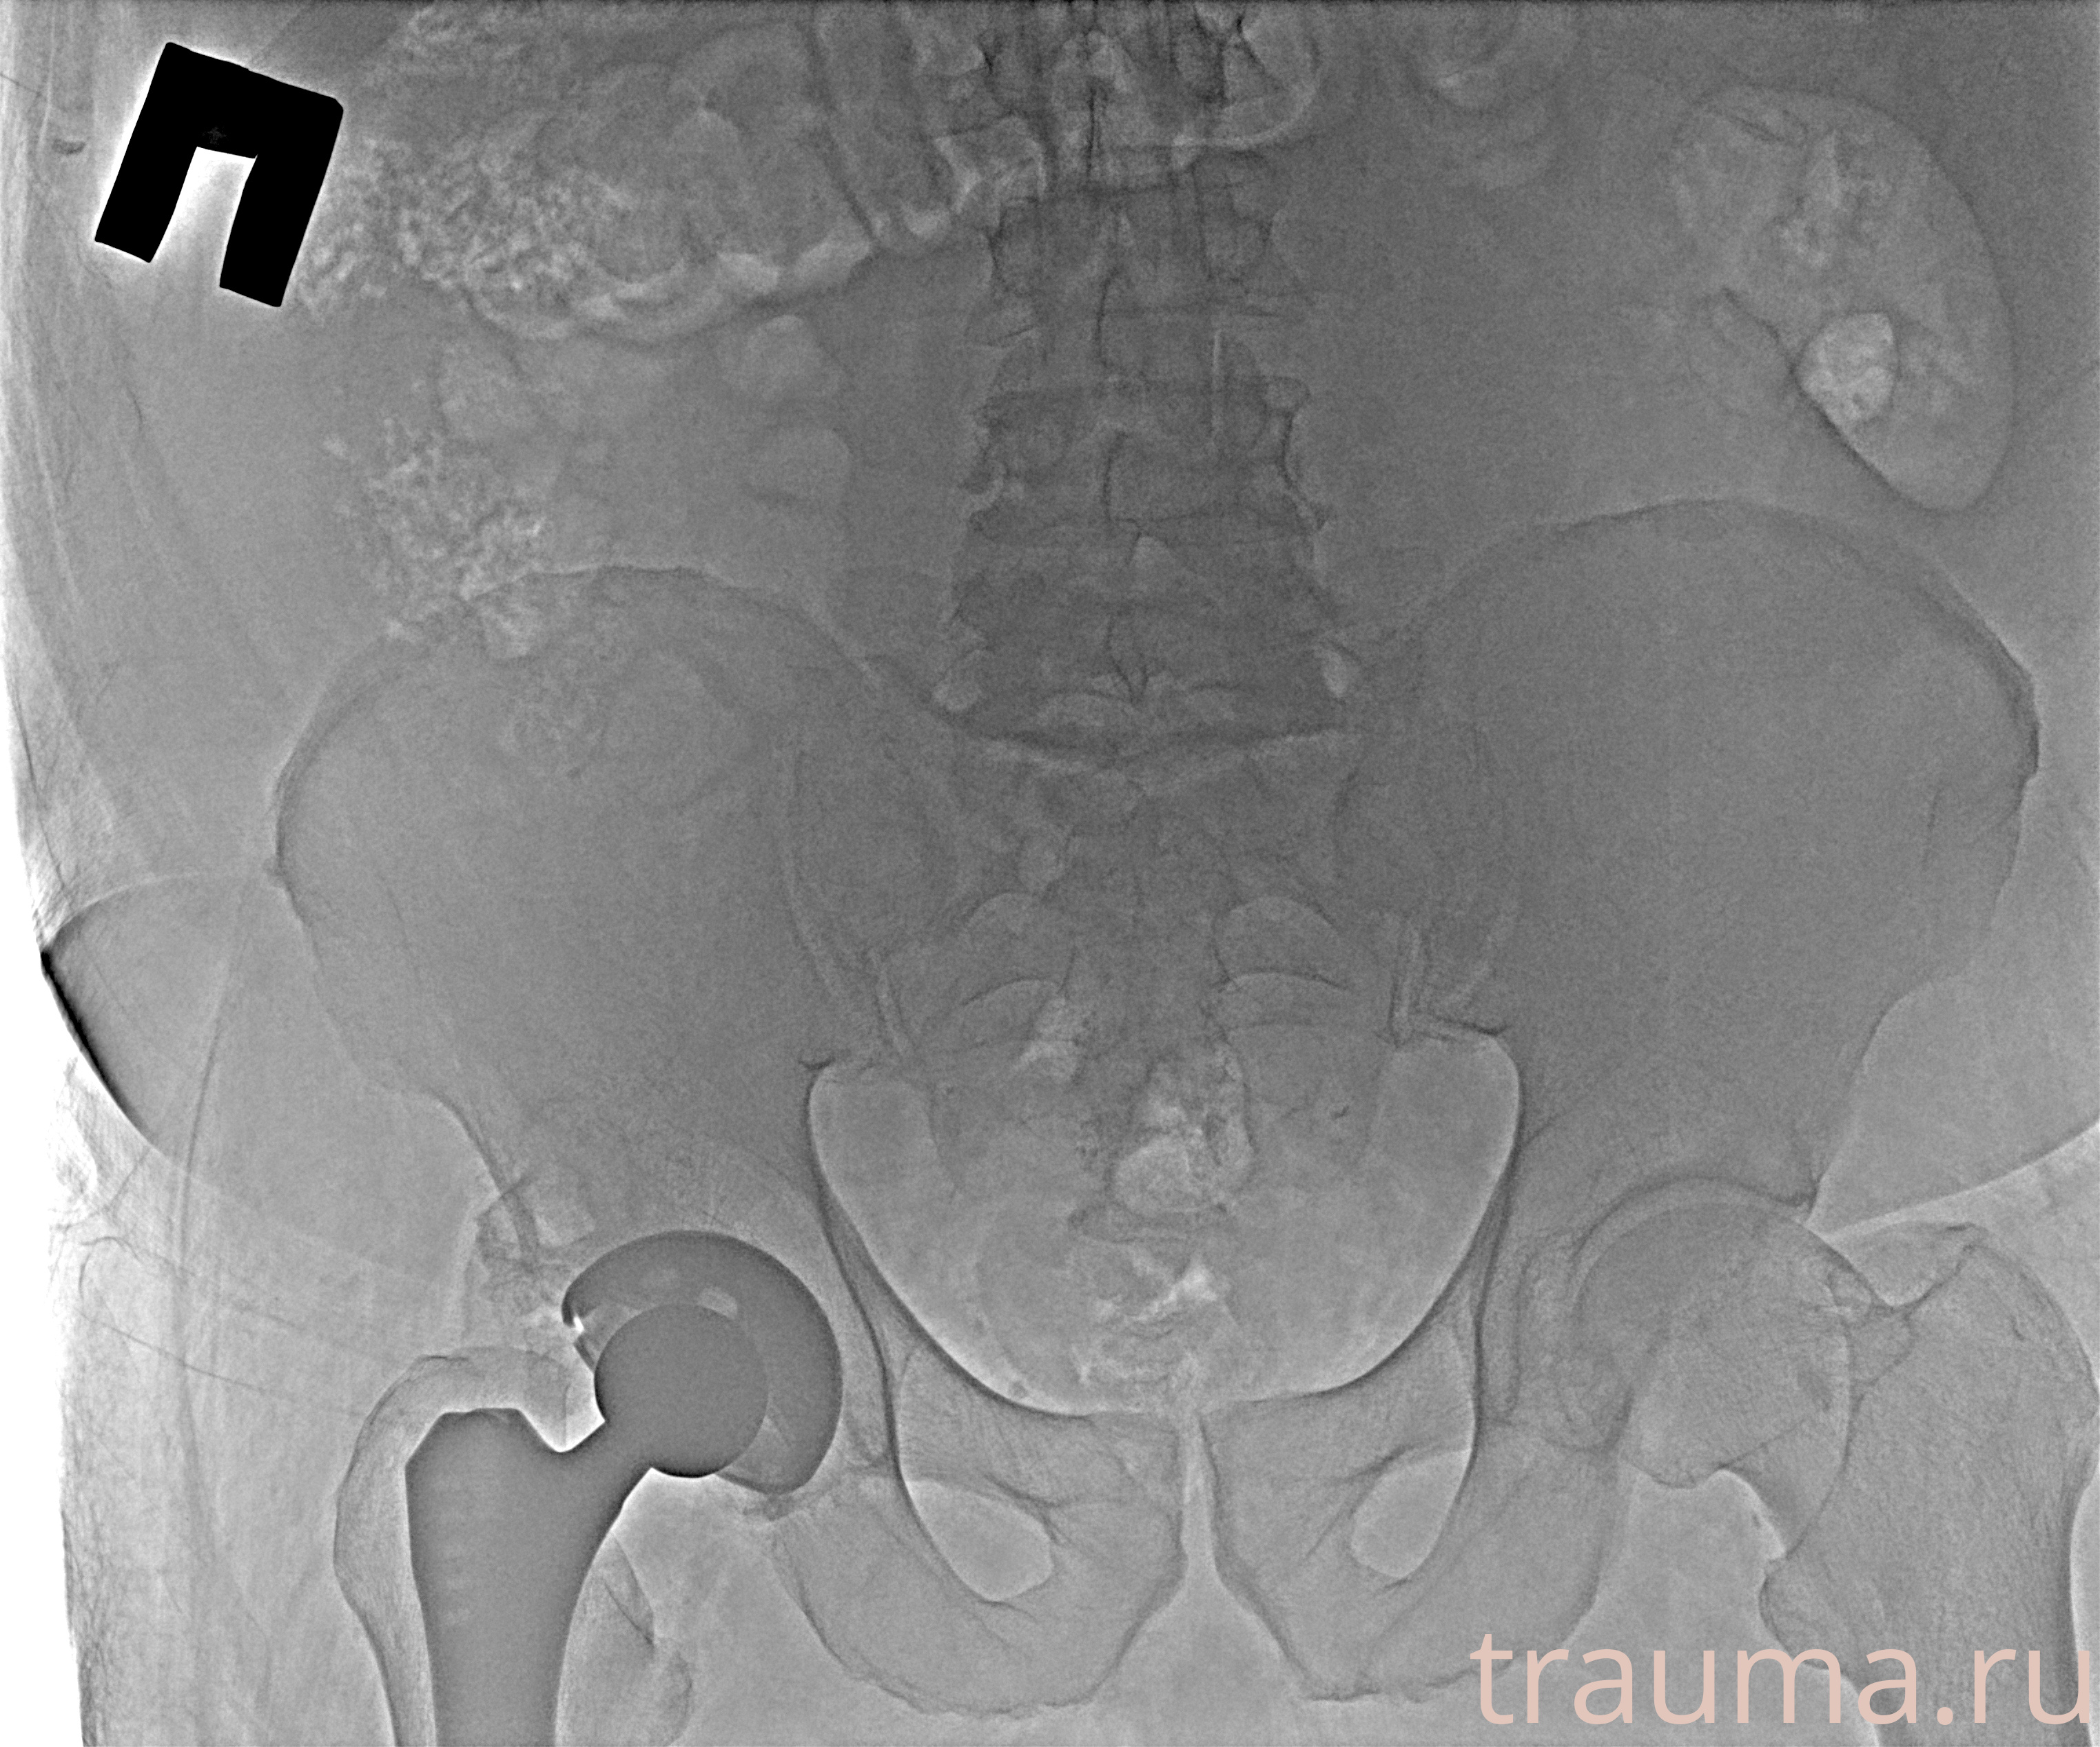

Рентгенограммы

Рентген на дому: по вашему адресу приезжает врач-рентгенолог, травматолог-ортопед с мобильным рентгеновским аппаратом, проводит диагностику травмы или заболевания, делает необходимые рентгенограммы, дает рекомендации по дальнейшему лечению. Получить качественные снимки в домашних условиях возможно благодаря уникальной методике, разработанной МосРентген Центром для института  Склифосовского